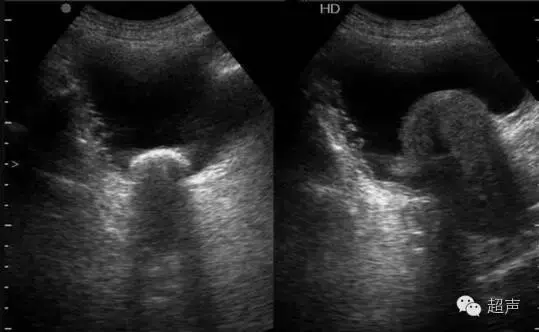

经腹部横切

经腹部前列腺纵切

经直肠前列腺纵切

经直肠前列腺横切